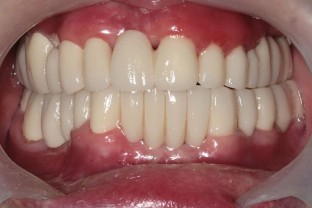

This report aims to present the clinical features, treatment approach, and management guidelines for plasma cell gingivitis (PCG) associated with nickel allergy. A 63-year-old woman was admitted to the clinic with complaints of gingival overgrowth and bleeding. Anamnesis and clinical examination revealed that she had been wearing metal-based fixed prostheses for 15 years. A complete blood count was performed and, after excluding malignancy, histopathologic evaluation revealed a diagnosis of PCG. A skin patch test confirmed nickel allergy, supporting the suspected link between the gingival condition and prolonged exposure to nickel-containing dental prostheses. Nickel levels in gingival tissues were evaluated using atomic absorption spectroscopy (AAS) before and after removal of restorations. AAS measurements detected 6.6 μg/g of nickel before removal and no more than blank analysis afterward. Following phase one and surgical periodontal treatment, and systemic steroid therapy, zirconium-supported prostheses were fabricated. The patient's gingival tissues returned to a healthy condition. This case report shows that PCG related to nickel allergy is characterised by gingival overgrowth with a fiery-red appearance. To confirm clinical findings, histopathological evaluation should include nickel quantification whenever possible. Treatment options should prioritise the elimination of nickel-containing prostheses, with substitution by all-ceramic restorations, to achieve resolution and prevent recurrence.